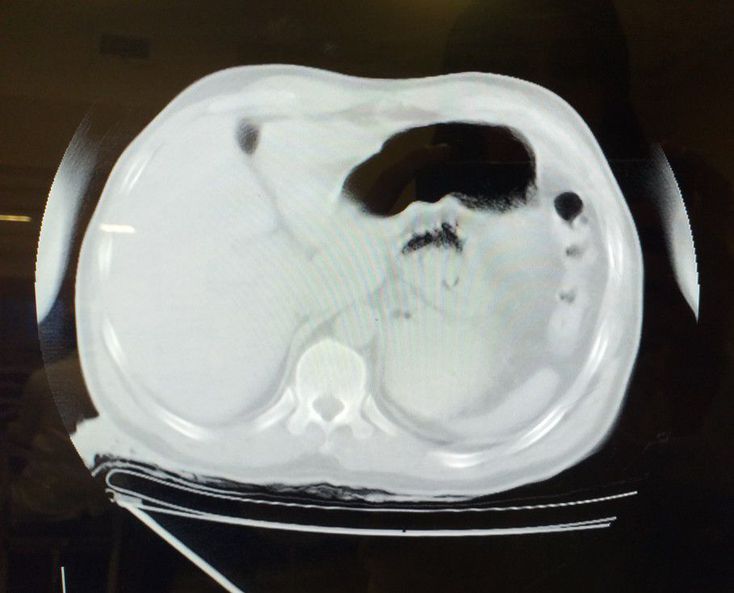

What is your diagnosis?

A 43 years old male with CA. SBP 12/70, EFAST: Negative